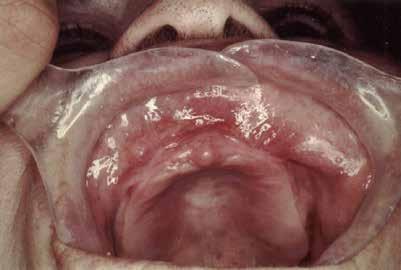

5. a–c ábrák: Granuloma fissuratum kimetszése szén-dioxid-lézerrel. Műtét előtti, közvetlenül műtét utáni, majd egy hónappal későbbi állapot.